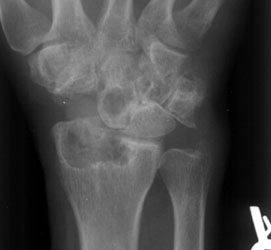

Silastic arthropathy can occur at any of the bones where there is a prosthetic

implant in place. However, involvement at the hand and wrist is most common

at the carpal bones, a location that is more susceptible to stress forces.

In decreasing order of frequency, scaphoid, lunate and scapholunate implants

are the most commonly affected carpal prostheses.

Radiographic Appearance:

At the site of the implant, an inflammatory process occurs in response to

the foreign particles, which are sloughed off of the implant. This leads to

erosion of bone and articular cartilage, and intraosseous cystic changes.

There can also be soft tissue swelling and calcifications in the immediate

area. Fractures and destructive changes of the prosthesis are sometimes present.